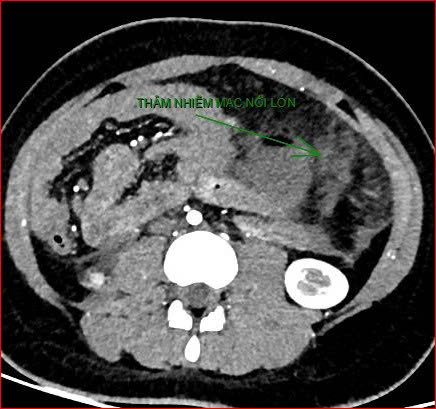

Khoảng 21 giờ 40, kết quả chụp CT cho thấy bệnh nhân rơi vào tình trạng cực kỳ nặng và hiếm gặp, bao gồm: xoắn dạ dày, nhồi máu thận trái, nhồi máu lách, viêm đầu tụy, viêm hỗng tràng, kèm dịch ổ bụng và tràn dịch màng phổi, trên nền bệnh nhân mắc hội chứng Down và tim bẩm sinh.

Hình ảnh chụp CT ổ bụng cho thấy dạ dày giãn lớn, xoắn bất thường; kèm tổn thương nhồi máu lách và viêm tụy trên nền ca bệnh hiếm, diễn biến đặc biệt nặng – Ảnh Bệnh viện cung cấp